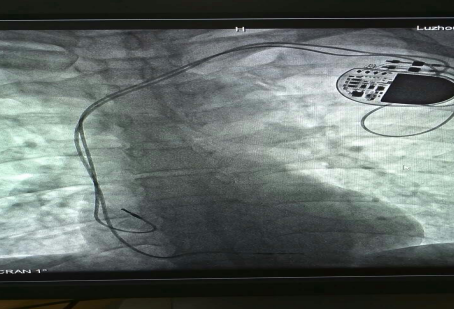

已安裝好的起搏系統(tǒng)

在征得患者及家屬的同意后,我院為其實施了雙腔永久心臟起搏器植入術,該手術在瀘州市市屬醫(yī)院中率先使用磁共振兼容起搏電極,為患者未來有可能接受的磁共振檢查創(chuàng)造了條件。

已安裝好的磁共振兼容起搏電極